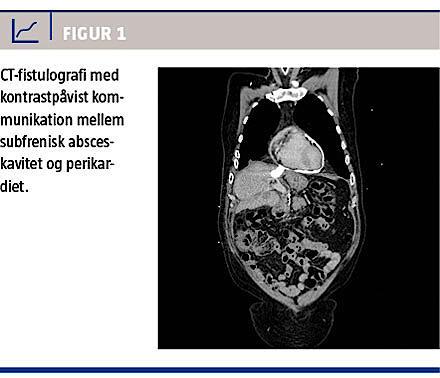

Patienten havde gennem et halvt år haft tiltagende smerter under højre kurvatur samt konstant trykkende brystsmerter og udstråling til begge skuldre. Et ekg viste ST-elevation i de prækordiale afledninger, men normale koronarmarkører. Resultatet var foreneligt med perikarditis, og en efterfølgende CT-fistulografi viste kommunikation mellem den subfreniske absceskavitet og perikardiet (Figur 1). Der blev efterfølgende foretaget MR-kolangiopankreatografi, hvorved man påviste en fistelgang fra galdevejene til føromtalte kavitet.